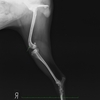

術前のレントゲン画像です。

膝蓋骨の外方脱臼によるもので、当初は指で整復できましたが、経過とともに骨の成長に対し、筋肉の成長が遅れてしまい、膝蓋骨が整復不能となり4ヶ月齢で早急に手術が必要と判断しました。